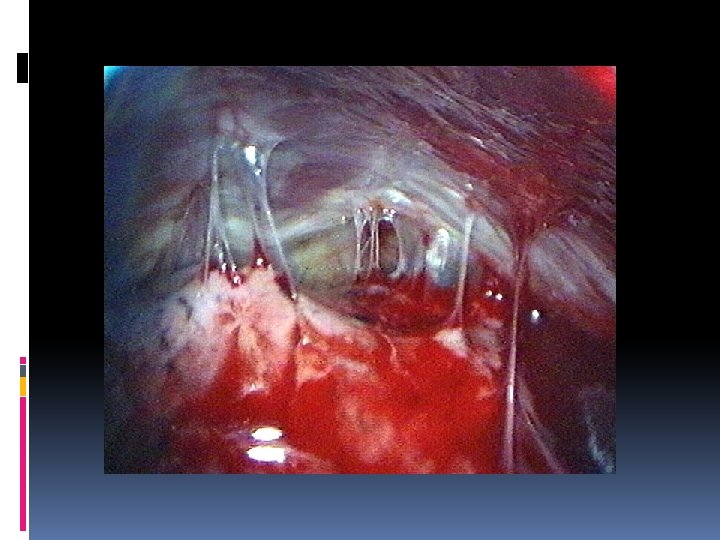

EMPIEMA PLEURICO VATS Essenziale per un trattamento adeguato e per prevenire la cronicizzazione è un drenaggio adeguato del cavo pleurico che permetta al polmone di riespandersi (obliterando il cavo pleurico) e che oggi viene attuato con chirurgia miniinvasiva. La VATS (Video Assisted Thoracic Surgery) permette di • evacuare completamente il contenuto dell’empiema • operare un’adeguata toilette • rottura delle eventuali sacche formatesi ed asportazione dello strato di fibrina dalla superficie del polmone • inserire visivamente il tubo di drenaggio nella posizione più appropriata

EMPIEMA PLEURICO VATS Tale procedura può essere, inoltre, messa in atto in anestesia locale potenziata (con sedazione più o meno marcata), (pazienti ad alto rischio). E’ importante che il drenaggio sia chiuso (con valvola ad acqua tipo Bulau), di diametro sufficiente e declive.